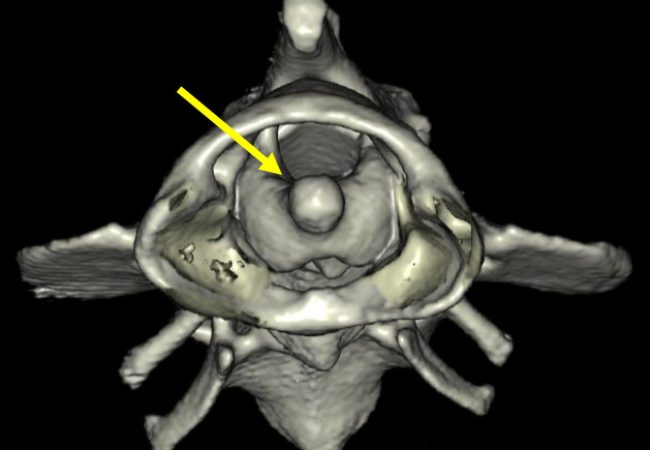

Instabilité atlanto-axiale sur un York Shire.

À gauche, reconstruction tridimensionnelle d’une luxation atlanto-axiale montrant clairement, grâce à la flèche, la dent de l’axis qui migre dans le foramen de l’atlas et exerce une compression directe sur la moelle épinière.

Au centre, modèle anatomique imprimé en 3D à partir des données scanner, utilisé pour analyser précisément l’anatomie du patient et planifier l’intervention chirurgicale.

À droite, plaque personnalisée imprimée en titane en 3D, conçue sur mesure à partir de la morphologie vertébrale du patient et utilisée pour assurer la stabilisation atlanto-axiale lors de la chirurgie.